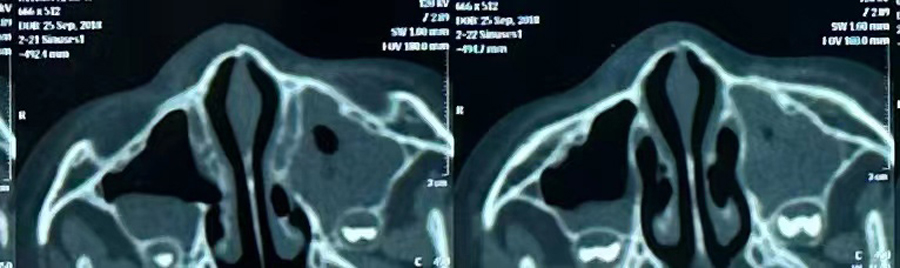

8月15日,彬彬家长在辗转多家医院后,听说德州扑克游戏网 有鼻骨骨折复位新技术,立即带彬彬赶到医院。此时,距离彬彬鼻骨骨折已经过去一周了。就诊时,彬彬鼻部肿胀已经消退了,能看到他的鼻梁是向左侧偏曲的,妈妈特别希望孩子的鼻梁能恢复到从前高挺、居中的状态。国家儿童医学中心、北京儿童医院耳鼻喉头颈外科常驻专家、德州扑克游戏网 副院长张薇,德州扑克游戏网 耳鼻喉科主任李莉萍为其进行鼻部检查,并结合鼻骨CT全面评估后,决定采用超声引导下鼻骨骨折复位术,以实现精准复位,使彬彬的面容不受影响。8月16日,张薇副院长、李莉萍主任及手术室、麻醉科医护人员组成手术团队,为彬彬进行手术。术中,医生在超声引导下应用复位器对游离骨片进行复位调节,使错位的鼻骨重新连续。10分钟后,手术顺利完成,复位后的鼻子外观无畸形。术后,彬彬接受抗感染治疗48小时,情况稳定,顺利出院。

相比较传统凭经验及手感的鼻骨复位术,超声引导下的手术复位能更精准定位到损伤部位,如医生的“透视眼”,实现手术可视化,使医生在术中可准确看到鼻骨断端的对合情况,在“精准、微创、美观”上得到极大优化和提升。患儿无伤口、恢复快。术前和术后鼻骨错位及对合情况B超均有图片准确显示,让家长也能看明白,患儿和家长的心理负担明显减轻不少,改善了就医体验。